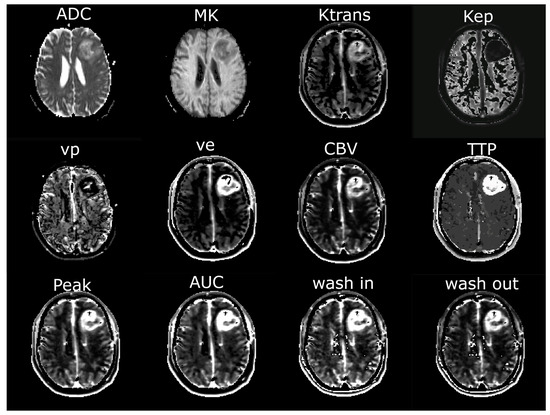

2.3. MR Imaging

2.4. Image Analysis